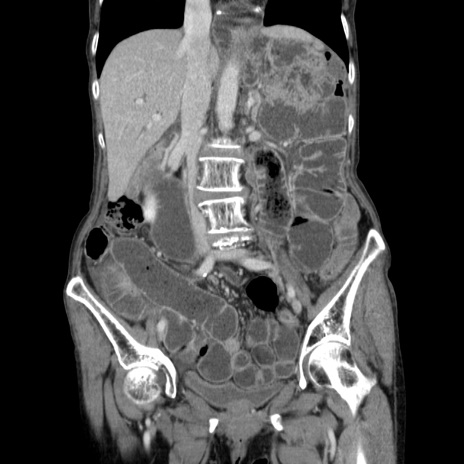

症例25(冠状断像)

【症例】80歳代女性

【主訴】胸のつかえ感

【現病歴】約9時間前に食後から胸のつかえた感じあり、嘔吐あり、来院。

【既往歴】胃癌(全摘)、胆摘、虫垂炎

【身体所見】心窩部に圧痛あり、反跳痛なし。

【データ】WBC 5700、CRP 0.05